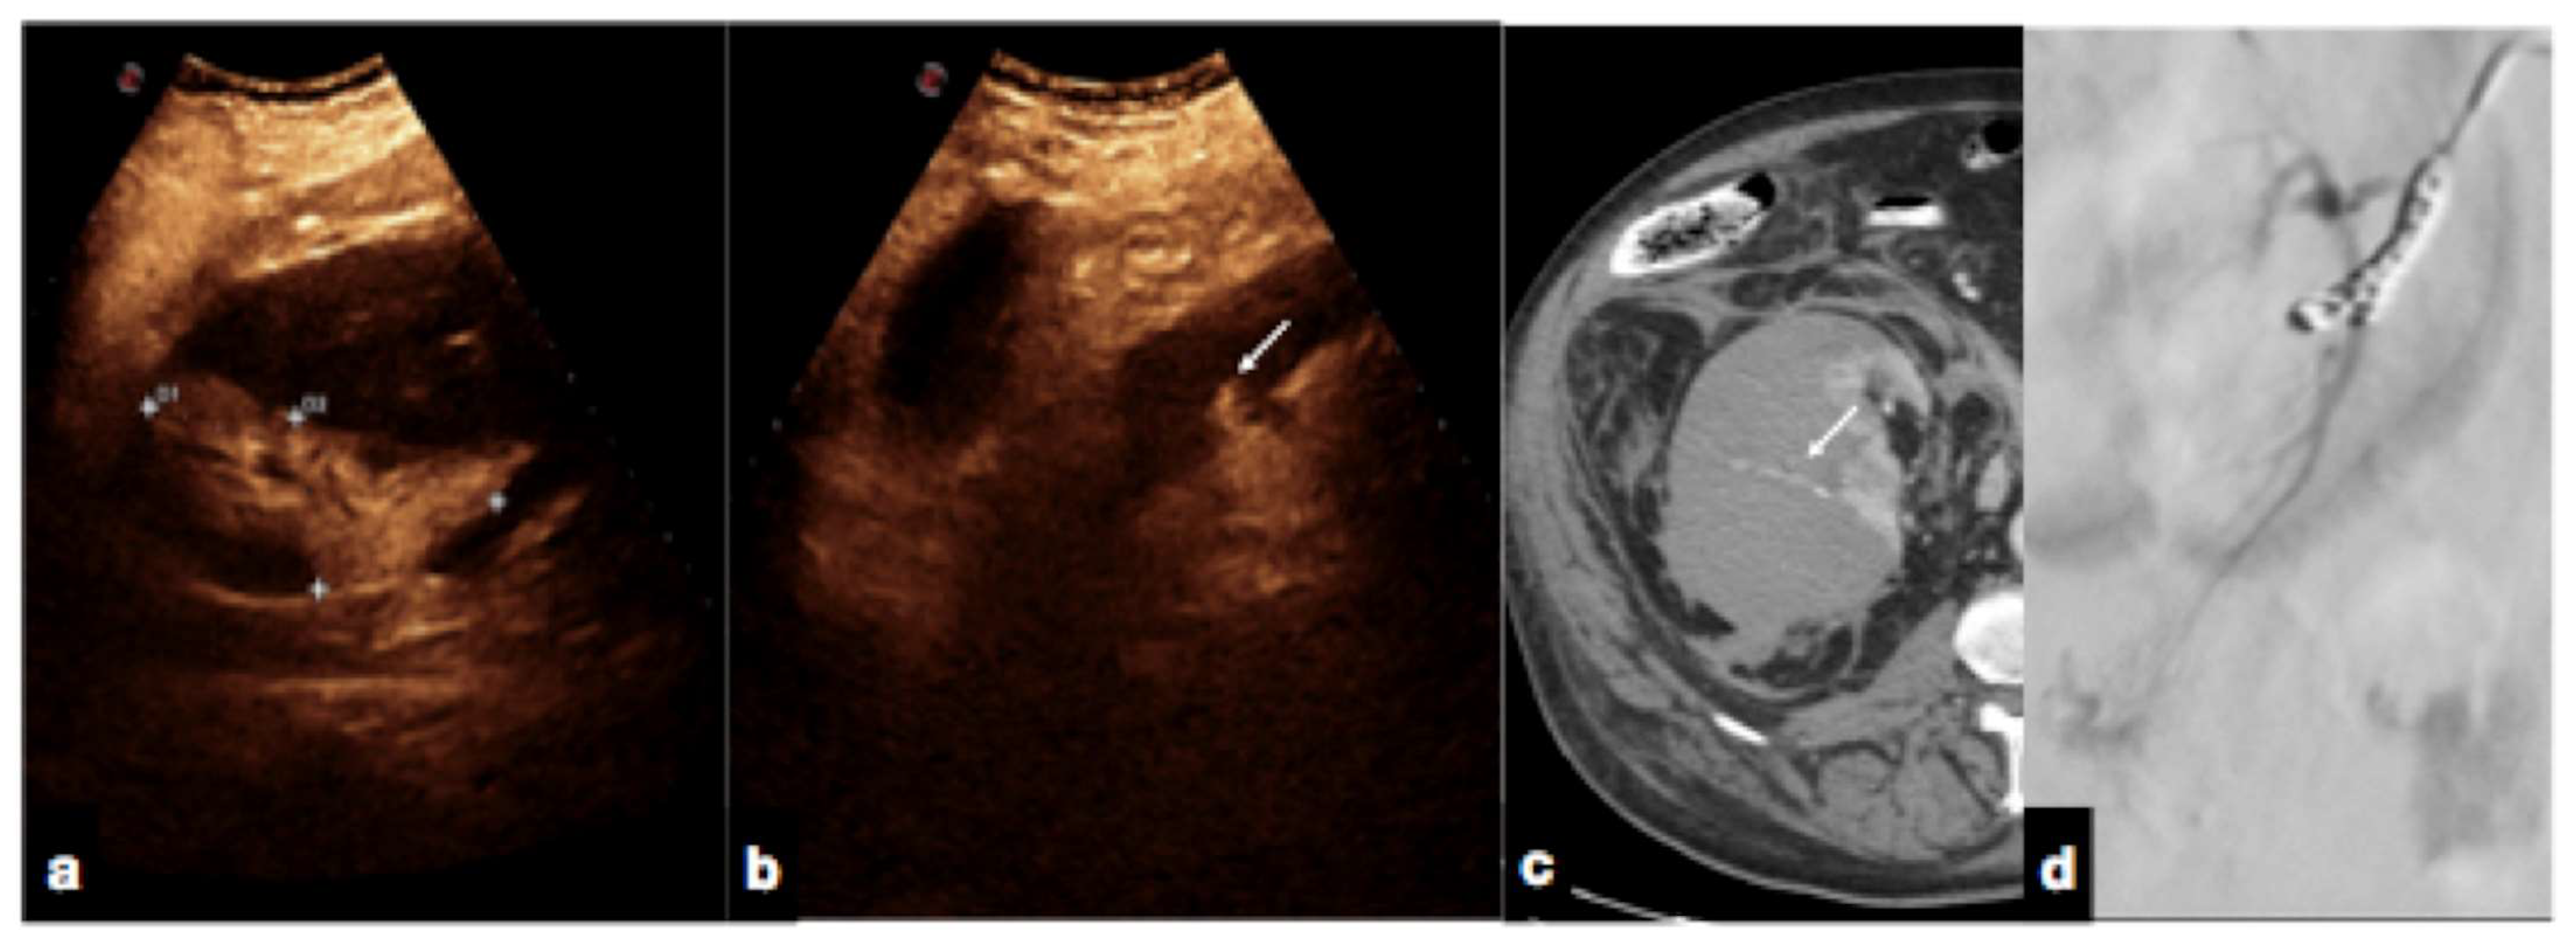

- Active bleeding:

- Contained vascular injuries:

- Iacobellis, F.; Iacobellis, F.; Scaglione, M.; Scaglione, M.; Brillantino, A.; Brillantino, A.; Scuderi, M.G.; Scuderi, M.G.; Giurazza, F.; Giurazza, F.; et al. The additional value of the arterial phase in the CT assessment of liver vascular injuries after high-energy blunt trauma. Emerg. Radiol. 2019, 26, 647–654. [Google Scholar] [CrossRef] [PubMed]

| 10–20 s (early) 20–40 s (late) | Arterial phase: best depiction of contained vascular injuries, such as pseudoaneurysms and arteriovenous fistulas in the early phase. |